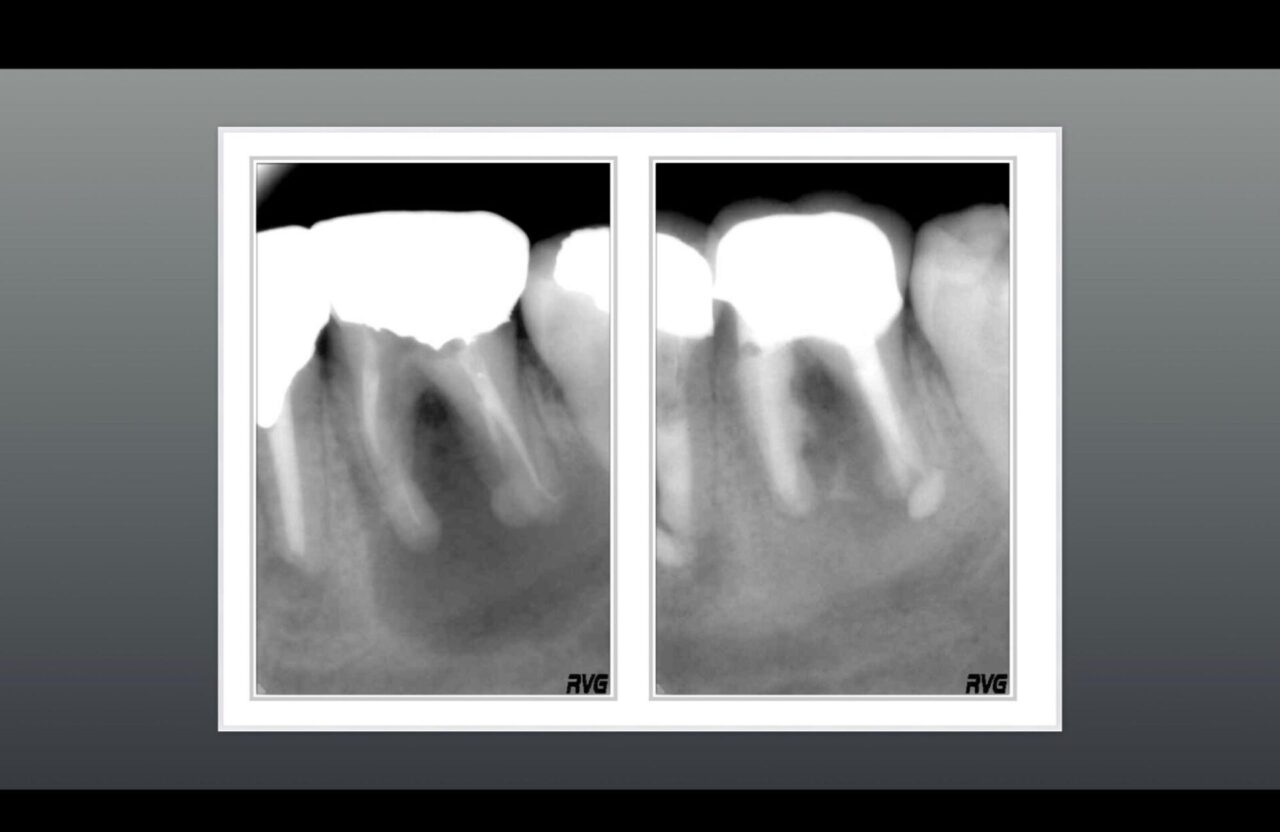

術前と術後のレントゲン①

術前と術後のレントゲン 大きな骨欠損が治り、骨の再生が確認できる。